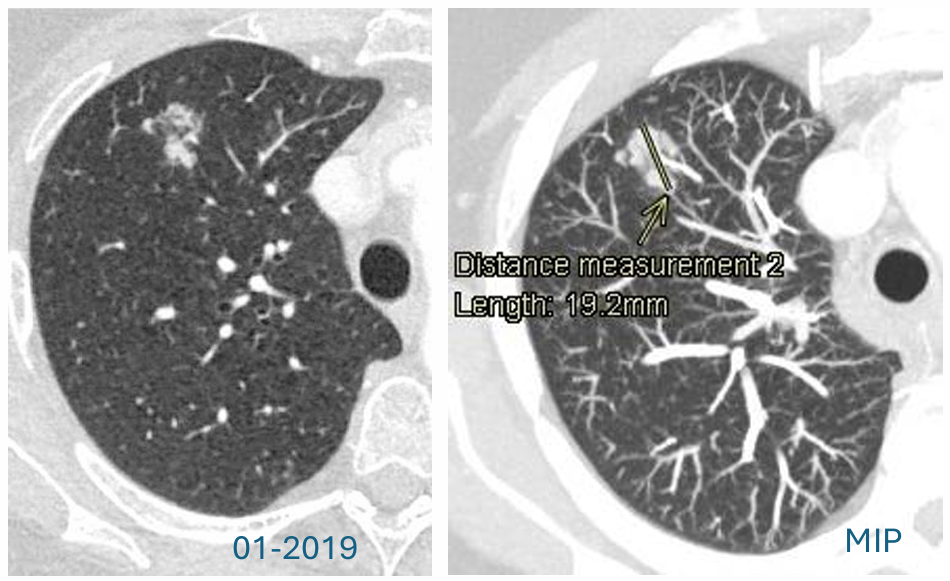

为明确该肺部结节性质,后续立即进行诊断性胸部CT扫描。2019年1月CT影像特征:CT(包括MIP重建)显示右肺上叶存在一个形态不规则的复杂结节。结节为亚实性病变,总直径长达19mm。关键风险特征:病灶包含一个直径大于8mm的实性成分。根据多项国际肺结节处理指南(如BTS、Fleischner指南)以及LungRADS 1.1(评分为4A/X类),直径>15mm或实性成分>8mm的亚实性结节,均被评估为高度可疑的恶性病变,需要立即进行诊断性检查(如活检)或密切的短期随访(如3-6个月复查)。

中期随访:误导性的病灶缩小

2019年11月,CT随访:距离初次发现约10个月后,CT复查显示令人意外的结果:结节明显缩小。影像表现:原有的亚实性(磨玻璃)成分变得“几乎难以辨认”。更重要的是,原先大于8mm的实性成分已缩小至仅3mm。这种显著的消退强烈指向炎性或感染性病变,在临床实践中,这通常被视为良性过程的有力证据,大多数情况下可能导致停止进一步的肿瘤相关随访。